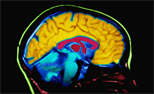

Alzheimer's and the brain

Just like the rest of our bodies, our brains change as we age. Most of us notice some slowed thinking and occasional problems remembering certain things. However, serious memory loss, confusion and other major changes in the way our minds work are not a normal part of aging. They may be a sign that brain cells are failing.

The brain has 100 billion nerve cells (neurons). Each nerve cell communicates with many others to form networks. Nerve cell networks have special jobs. Some are involved in thinking, learning and remembering. Others help us see, hear and smell. Still others tell our muscles when to move. In Alzheimer’s disease, as in other types of dementia, increasing numbers of brain cells deteriorate and die.